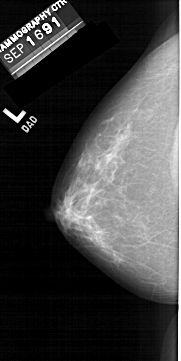

A_1456_1.RIGHT_MLO

RIGHT_MLO LINES 6091 PIXELS_PER_LINE 3571 BITS_PER_PIXEL 12 RESOLUTION 43.5 OVERLAY